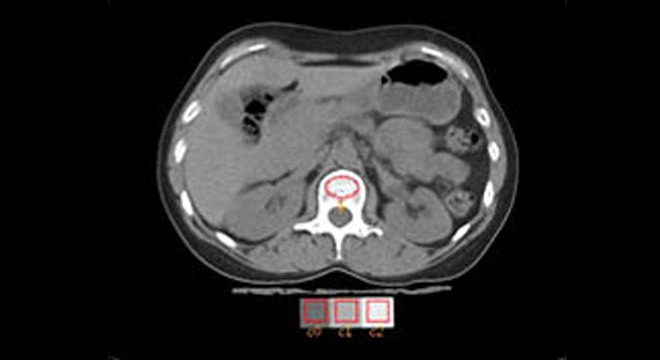

• Messung der Knochendichte mit speziellem Röntgenverfahren oder mit quantitativer Computertomographie

• Röntgenaufnahmen zeigen Knochenveränderungen im fortgeschrittenen Stadium